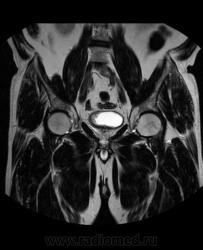

Для динамического контрастирования требуется инъектор, у нас с ним технические неполадки, поэтому контрастное вещество вводим от руки. Но в данном случае четко видно проростание опухолевого компонента через мышечный слой мочевого пузыря, даже некоторой инфильтрацией паравезикальной клетчатки. По гистологии плоско-клеточный рак. У пациента множественные метастазы в легких.